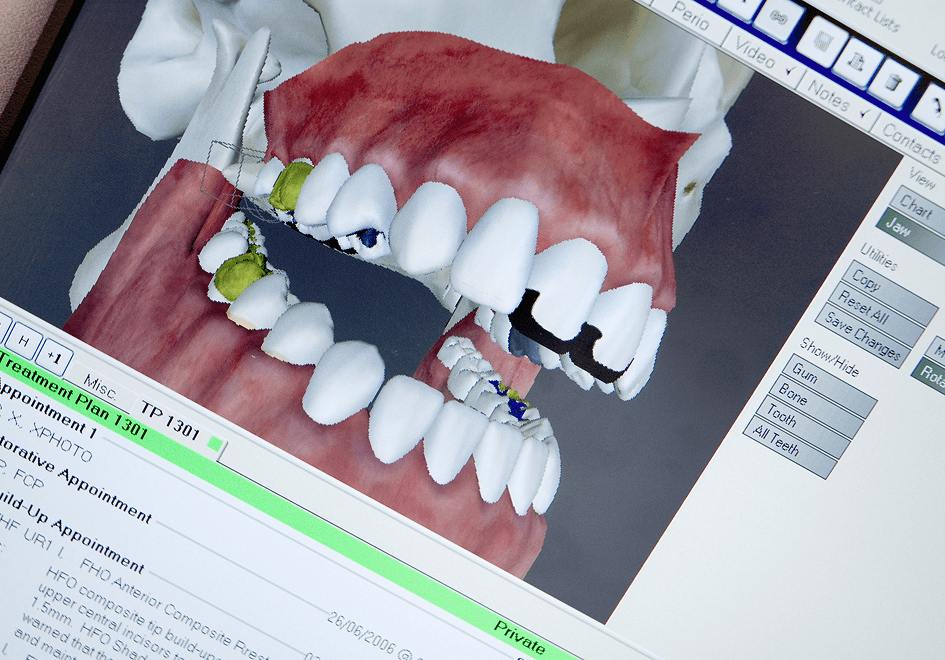

Treatment at our clinic is offered on a private basis and also to PRSI-qualified patients. Services include all routine dental treatment (examinations, cleanings, fillings etc.), cosmetic dentistry such as teeth whitening, bonding and porcelain veneers as well as more advanced procedures including the provision of crowns and bridges and dental implants.

We also provide specialist prosthodontic services here at Shelbourne so we can cater for those patients requiring extensive dental treatment such as full mouth reconstructions, severe wear cases and advanced cosmetic dentistry.

Listed below are some of the treatments and services we offer. We’ve also included several real life ‘case studies’ which demonstrate what can be encountered, and how we’ve managed the case.